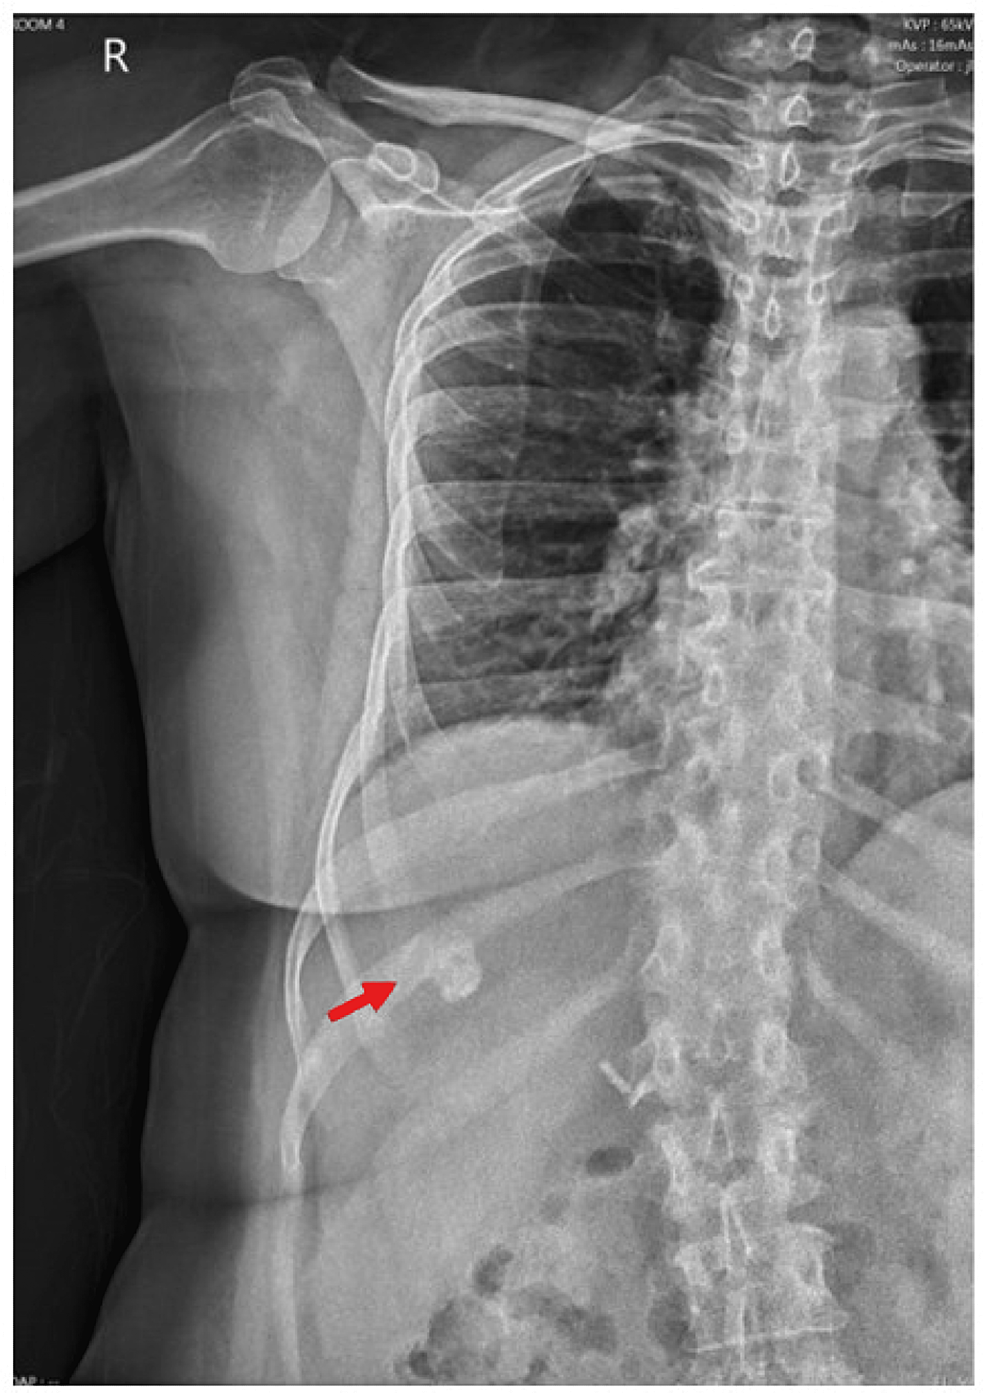

From www.researchgate.net

CT scan showing a linear calcification consistent with liver fibrosis How To Cure Liver Calcification learn about the causes, symptoms, and treatments of different types of calcium deposits in your body, such as ato,. if the symptoms have started to present, and the calcified nodules are larger and caused due an underlying infection that has started to affect regular. learn about the causes, symptoms and treatments of liver disease, including blood tests,. How To Cure Liver Calcification.